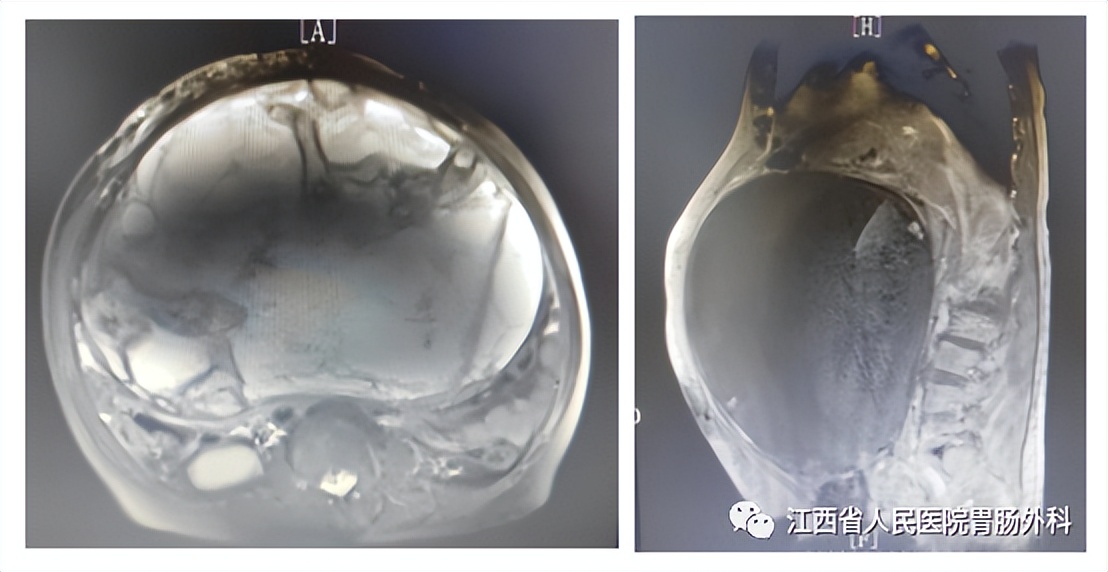

入院后完善相关检查:血红蛋白:82g/L;CA125:127.8U/ml;白蛋白 33.7g/L。腹部CT:腹腔巨大占位(图2),考虑来源于胃体间质瘤可能;脾大;腰2、3、4椎体失稳;头颅+腹部MR:腹腔内巨大囊实性占位,考虑胃来源间质瘤可能(图3);右侧颈内动脉未见显影,考虑闭塞可能性大,左侧颈内动脉多发结节状突起。术前诊断:1.胃恶性肿瘤(巨大间质瘤?),2.高血压3级(极高危组),3.中度贫血,4.右侧颈内动脉闭塞,5.脾大,6.腰椎不稳定。

图3(术前MR)